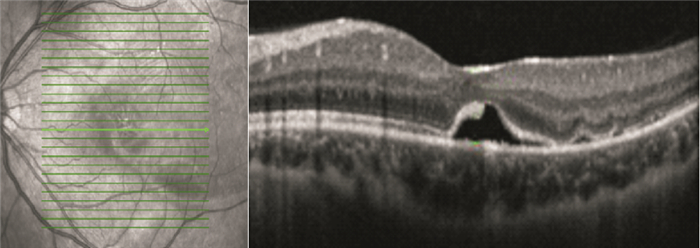

OCT檢查發現,手術后視網膜下液吸收時間1~13個月,平均視網膜下液吸收時間(7.82±3.52)個月。手術后12個月,42只眼中,視網膜下液吸收37只眼,占88.1%;視網膜下液殘留5只眼,占11.9%。視網膜下液吸收37只眼中,視網膜微結構正常15只眼;神經上皮層黃斑囊樣水腫5只眼(圖 1);光感受器內外節連接(IS/OS)斷裂12只眼;IS/OS和外界膜(ELM)斷裂5只眼(圖 2)。

患眼OCT像。IS/OS聯合ELM斷裂

患眼OCT像。IS/OS聯合ELM斷裂

OCT檢查發現,手術后視網膜下液吸收時間1~13個月,平均視網膜下液吸收時間(7.82±3.52)個月。手術后12個月,42只眼中,視網膜下液吸收37只眼,占88.1%;視網膜下液殘留5只眼,占11.9%。視網膜下液吸收37只眼中,視網膜微結構正常15只眼;神經上皮層黃斑囊樣水腫5只眼(圖 1);光感受器內外節連接(IS/OS)斷裂12只眼;IS/OS和外界膜(ELM)斷裂5只眼(圖 2)。

患眼OCT像。IS/OS聯合ELM斷裂

患眼OCT像。IS/OS聯合ELM斷裂

光感受器細胞IS/OS連續及ELM完整,是實現正常視覺的重要條件[8]。惠延年[9]認為視網膜脫離復位后,隨著IS/OS修復,視力逐漸恢復。而當IS/OS聯合ELM受損時則預示著這種損害擴展到細胞體及Müller細胞。因ELM較IS/OS更靠近細胞核,ELM受損代表光感受器細胞損傷加重,并且已有研究表明,單純IS/OS斷裂可以自行恢復,而聯合ELM受損后,IS/OS不能恢復[10, 11],表明ELM損傷對在IS/OS損傷修復中的作用,并且側面反映出ELM損傷對IS/OS的影響。本研究IS/OS斷裂12只眼中,聯合ELM破壞5只眼,印證了Delolme等[12]觀察的IS/OS受損多聯合ELM損傷的觀點。